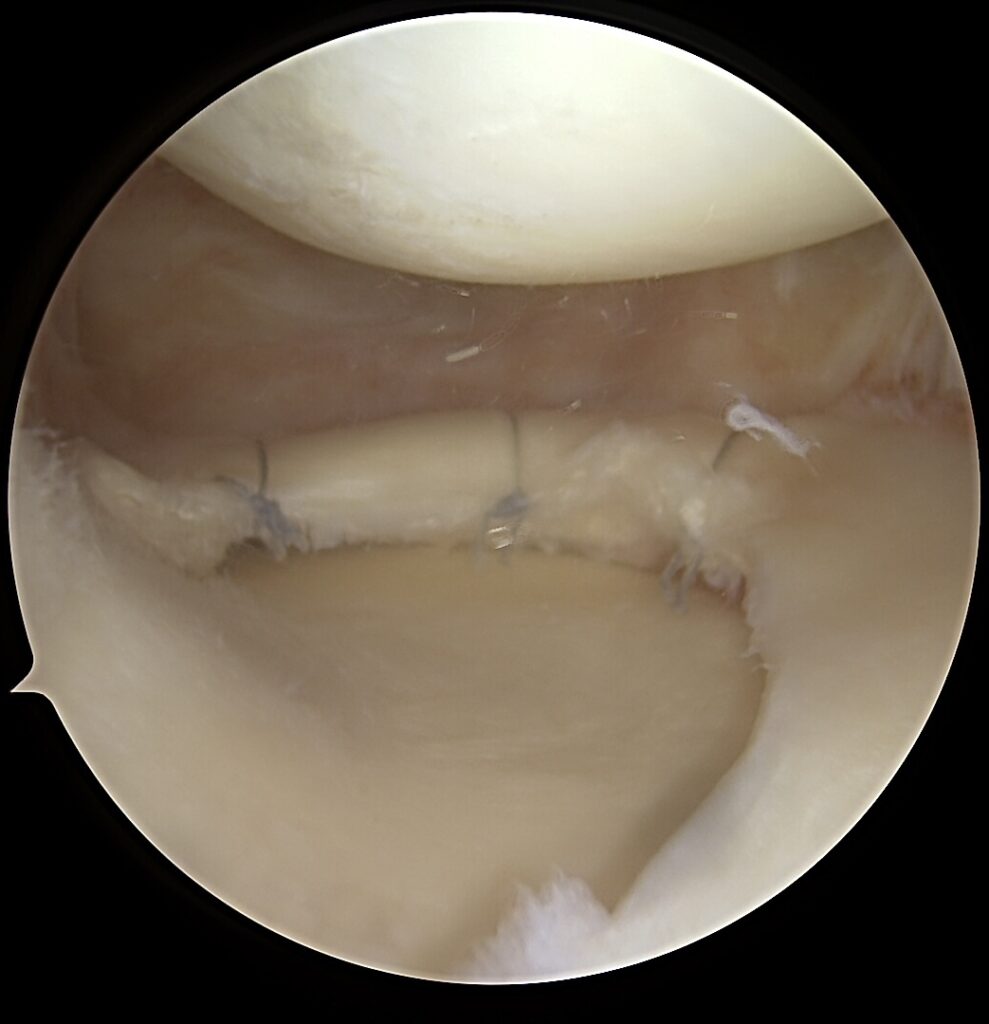

Blauzdos kaulų išnirimas – viena sunkiausių ortopedinių traumų, dažniausiai lydima kelių kelio sąnario raiščių plyšimų, kraujagyslių ir nervų pažeidimų rizikos. Tokios traumos dažnos po aukštos energijos sužalojimų: eismo įvykių, kritimų iš aukščio ar kontaktinio sporto. Sunki kelio sąnario trauma: blauzdos kaulų išnirimo gydymas atliekant daugiaraištę kelio rekonstrukciją – yra iššūkis ne tik ortopedo komandai, bet ir pačiam pacientui.

Sunki kelio sąnario trauma: blauzdos kaulų išnirimo gydymas atliekant daugiaraištę kelio rekonstrukciją nėra lengva chirurginė procedūra, reikia labai tiksliai žinoti kelio anatomiją.

🦴 Modernus chirurginis sprendimas – anatominių struktūrų rekonstrukcija

✔️ Priekinio kryžminio raiščio (ACL) ir užpakalinio kryžminio raiščio (PCL) rekonstrukcija – atstato priekinį ir užpakalinį stabilumą

✔️ Posteromedialinio nestabilumo rekonstrukcija – būtina apsaugoti kryžminius raiščius nuo pakartotinio nepakankamumo

✔️ V formos MCL ir POL rekonstrukcija – atkuria vidinį stabilumą ir rotacinę kontrolę

👉 V formos rekonstrukcija leidžia tiksliai atkartoti natūralią raiščių anatomiją, sumažinti liekamąją nestabilumo riziką.